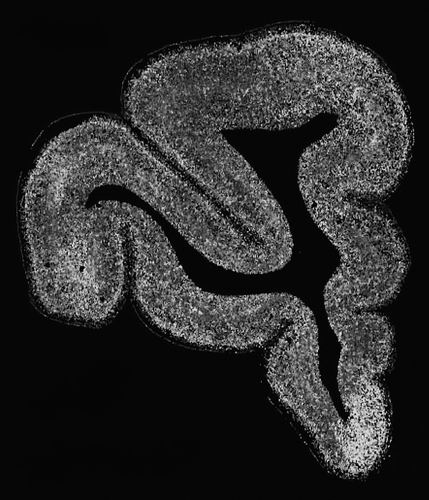

与抑郁症相关神经细胞在食蟹猴内侧前额叶皮层深部的分布。课题组供图

在研究精神分裂症、抑郁症等复杂脑疾病及智商等性状时,团队借助gsMap探索了不同脑区与精神疾病及认知功能相关的细胞。他们发现,谷氨酸能神经元在多种脑疾病和性状中关联显著。结合药物数据库,他们发现内侧前额叶深部的高表达基因在精神药物靶点基因中的富集程度是其他大脑皮层区域的16倍,凸显了该脑区对抑郁症干预和靶向治疗的关键作用。